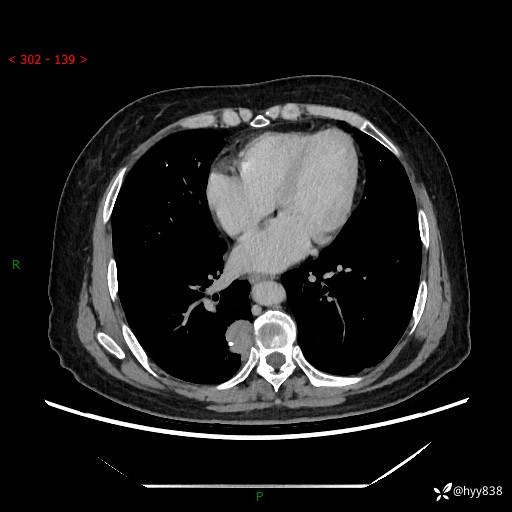

增强动脉期+静脉期

两期CT值:55Hu 53hu